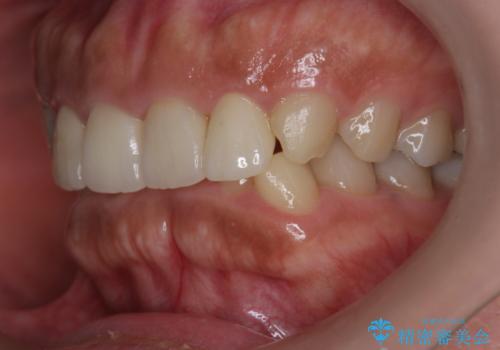

- 他院で昨年治療したセラミッククラウンが欠け、審美性の改善を求めて来院されました。

噛み合わせからクラウンが欠けやすい状態だったので、欠けにくく強度に優れるフルジルコニアクラウンで審美性を改善します。

フルジルコニアクラウンは若干透明感に劣る反面、強度に優れ大きな力のかかる部位に有効な補綴方法です。